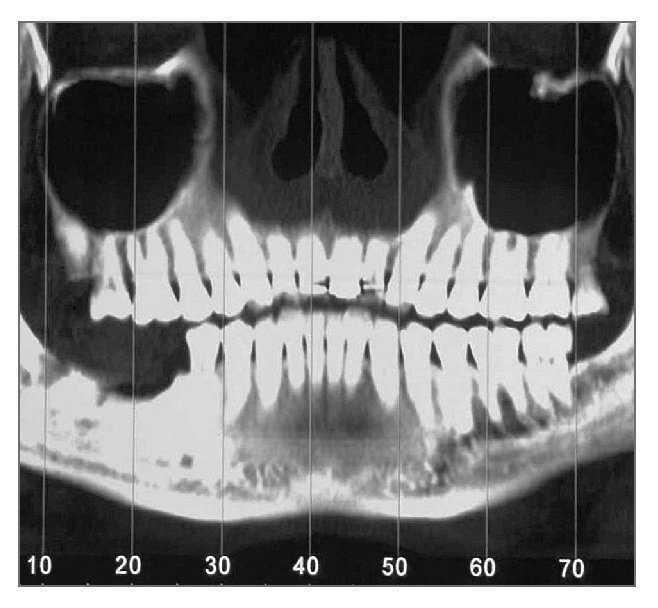

Un hombre de 44 años de edad se presentó en el Departamento de Periodoncia del Hospital Capital de las Fuerzas Armadas, Gyenggido, de Corea, para tratamiento de la pérdida de sus molares inferiores derechos (fig. 1). La historia clínica no presentaba datos de interés y el paciente no tomaba ninguna medicación que pudiera interferir con la curación de las heridas. El paciente fue remitido al Departamento de Prótesis para una evaluación más completa y planificación del tratamiento. Se le dieron explicaciones respecto a su estado actual, plan de tratamiento y procedimientos que realizar. Tras consultarlo con él se planificó un tratamiento con colocación de implantes e injerto óseo simultáneo. Se obtuvo consentimiento informado del paciente.

Figura 1 (izquierda). Caso 1. Imagen transversal de una tomografía computarizada antes del tratamiento.